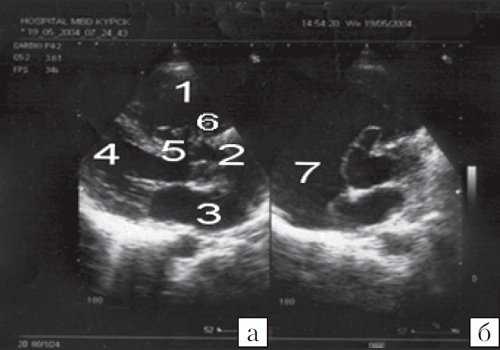

При эхокардиографии определялся дефект межжелудочковой перегородки, локализовавшийся в ее перимембранозной части (рис. 4). На это указывало более медиальное (ближе к сектальной створке трикуспидального клапана) расположение дефекта при локации сердца по короткой оси из парастернальной позиции. Дефект был закрыт мембраной, в результате чего сформировалась аневризма межжелудочковой перегородки, которая пролабировала в полость правого желудочка. Кроме того, у пациента имела место аномалия митрального клапана в виде наличия его двойного отверстия (рис. 5). Регистрировалась регургитация различной степени через атриовентрикулярный и аортальный клапаны. Проходимость аневризмы межжелудочковой перегородки не была выявлена.

![Эхокардиограмма больного C (а - парастернальная позиция по длинной оси, б - парастернальная позиция по короткой оси на уровне аорты)]()

Рис. 4. Эхокардиограмма больного С.

а) - парастернальная позиция по длинной оси;

б) - парастернальная позиция по короткой оси на уровне аорты.1 - правый желудочек; 2 - аорта; 3 - левое предсердие; 4 - левый желудочек; 5 - дефект межжелудочковой перегородки; 6 - аневризма межжелудочковой перегородки; 7 - правое предсердие.

![Эхокардиограмма больного С (парастернальная позиция по короткой оси на уровне митрального клапана)]()

Рис. 5. Эхокардиограмма больного С. (парастернальная позиция по короткой оси на уровне митрального клапана).

1 - правый желудочек; 2 - левый желудочек; 3 - аневризма межжелудочковой перегородки; 4 - митральный клапан с двойным отверстием.

Следовательно, в данном случае имелся дефект межжелудочковой перегородки со спонтанным его закрытием, сочетавшийся с аномалией митрального клапана (двойное отверстие митрального клапана), недостаточностью аортального, митрального и трикуспидального клапанов.